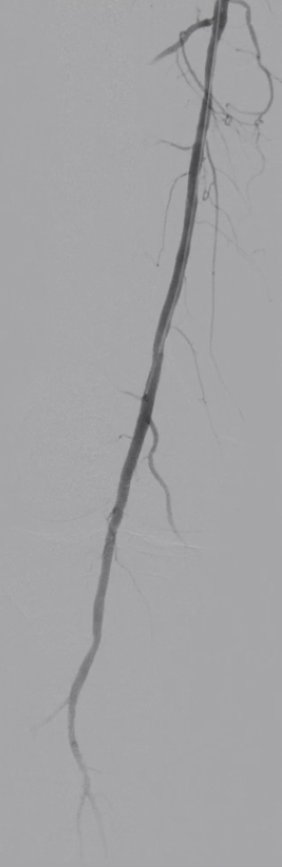

手术结果:

血流通畅,解剖与功能双重改善

最终造影显示:支架定位准确、形态良好,股浅动脉、腘动脉及膝下动脉显影清晰,血流通畅。